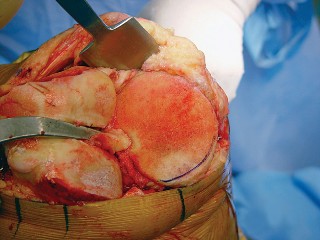

هذه الجراحة ليست مجرد استبدال للمفصل التالف، بل هي عملية تصحيحية شاملة تهدف إلى إعادة المحاذاة الطبيعية للركبة والتخلص من الانحراف التقوسي الذي يسبب الألم ويُسرّع من تدهور المفصل. بفضل الخبرة الواسعة للأستاذ الدكتور محمد هطيف التي تمتد لأكثر من عقدين من الزمن كأستاذ جامعي وجراح عظام متخصص، وباستخدامه لأحدث التقنيات الجراحية مثل الجراحة المجهرية وتنظير المفصل بتقنية 4K وزراعة المفاصل المتقدمة، يتمكن مرضى خشونة الركبة التقوسية في صنعاء من استعادة حركتهم الطبيعية والعيش بلا ألم.

يُعد الانحراف التقوسي مشكلة شائعة وقد يكون خلقيًا (موجودًا منذ الولادة)، ولكنه غالبًا ما يتطور بمرور الوقت نتيجة لخشونة الركبة المتقدمة، حيث يؤدي التآكل غير المتساوي للغضروف إلى تفاقم التشوه. تصحيح هذا الانحراف هو جوهر جراحة استبدال مفصل الركبة التقوسي، وهو ما يتقنه الأستاذ الدكتور محمد هطيف لضمان استقرار المفصل وطول عمره.